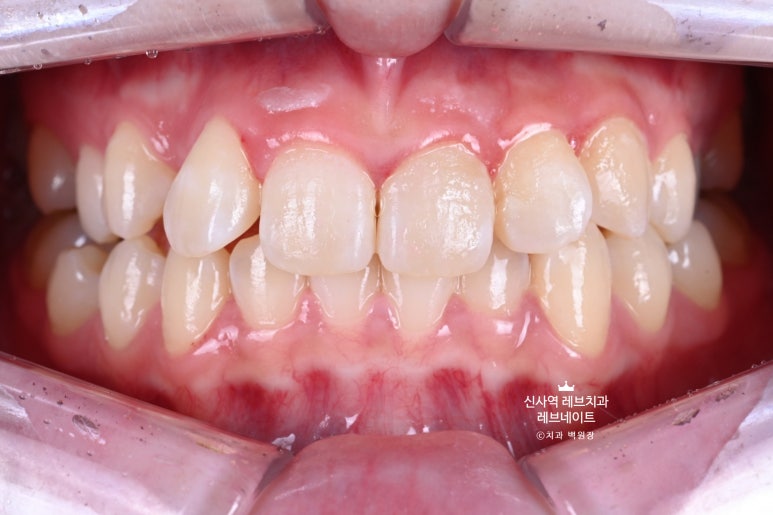

그냥 얼핏 보기엔 뭐.. 치열이 조금 틀어져 있네? 이 정도라고 생각이 드실텐데요

(저 또한 그랬습니다.)

이게 왠걸 ! 고개를 돌려보니 치아가 하나 없는겁니다...

어딨지? 하고 보니,

오른쪽 송곳니가 보다 안쪽에 있는 부정교합이라, 마치 치아하나가 없는 것 처럼 보이는 상태셨어요.

정면만 딱 보면 안보이는 것 같은데, 얘기하거나 웃을 때 엄청 잘 보이는 앞니 사이 공간이 있는거에요..

그리고 잘 보면, 치아들이 조금 뻐드러져 있기도 하고.. 뭔가 돌아가 있기도 하고..